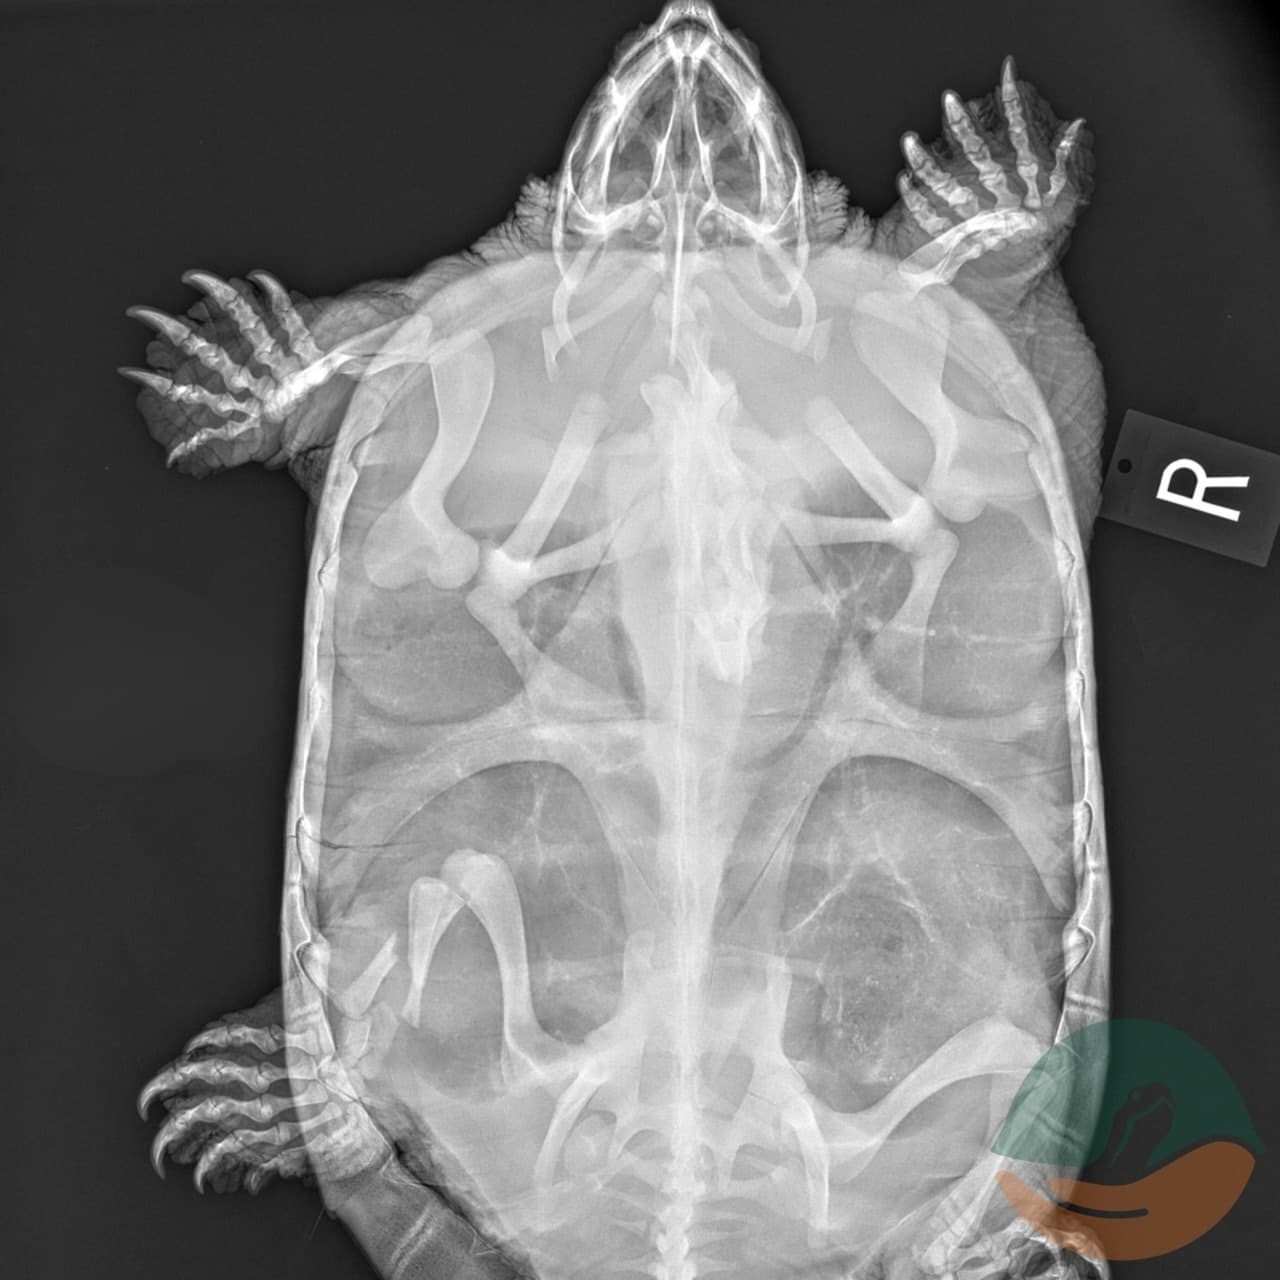

This escape artist version of Quinn is a totally different turtle from the Quinn who was admitted in June 2023. Quinn had a rough start to the rehab journey. He had severe fractures all over his body. His front leg was swollen and he did not use it - it appeared broken, but radiographs confirmed there were no breaks to his front limbs, just fractures. His back leg however was broken, and it was a bad break. The front of his carapace (the top part of the shell) had fractures as well, and his eye on the same side was swollen, and he often kept it closed. The rear carapace had fractures as well. Poor Quinn had injuries on just about every part of his body.